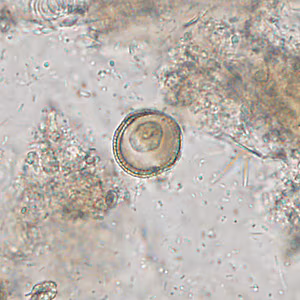

Case #309 – October, 2011

A 19-year-old male presented to his health care provider with moderate abdominal cramping and intermittent diarrhea that started approximately one week following a camping trip in the southeastern United States. A fecal specimen in 10% formalin was submitted for ova-and-parasite (O&P) examination. A formalin-ethyl acetate (FEA) concentrate was performed and Figures A and B show what was observed at 400x magnification in a wet mount preparation. The objects measured 17-20 micrometers on average. What is your diagnosis? Based on what criteria?

Figure A